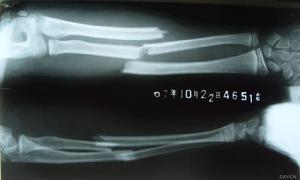

下尺橈關節脫位一、伸直型骨折

傷後局部疼痛,腫脹,可出新典型畸形姿勢,即側面看呈“銀叉”畸形,正面看呈“槍刺樣”畸形,檢查局部壓痛明顯,腕關節活動障礙。X線拍片可見骨折遠端向橈、背側移位,近端掌側移位,因此表現出典型的畸形體徵,可通知伴有下尺橈關節脫位。

二、屈曲型骨折

受傷後,腕部下垂,局部腫脹,腕背側皮下淤斑,腕部活動受限,檢查局部有明顯壓痛。X線拍片可發現典型移位,近折噸向背側位,遠折端向掌側、橈側移位,與伸直型骨折移位方向相反,成為反Colles骨折或Smith骨折。

三、橈骨遠端關節面骨折伴腕關節脫位

臨床上表現為與Colles骨折相似的“銀叉”畸形及相應的體徵。X線拍片可發現典型的移位,當跌倒時,腕關節屈曲手背著地受傷,可發生與手術相反的橈骨下端掌側關節面骨折及腕骨向掌側移位。這些骨折較少見,臨床上長漏斬或錯誤診斷為腕關節脫位,只要仔細閱讀X線片診斷並不困難。